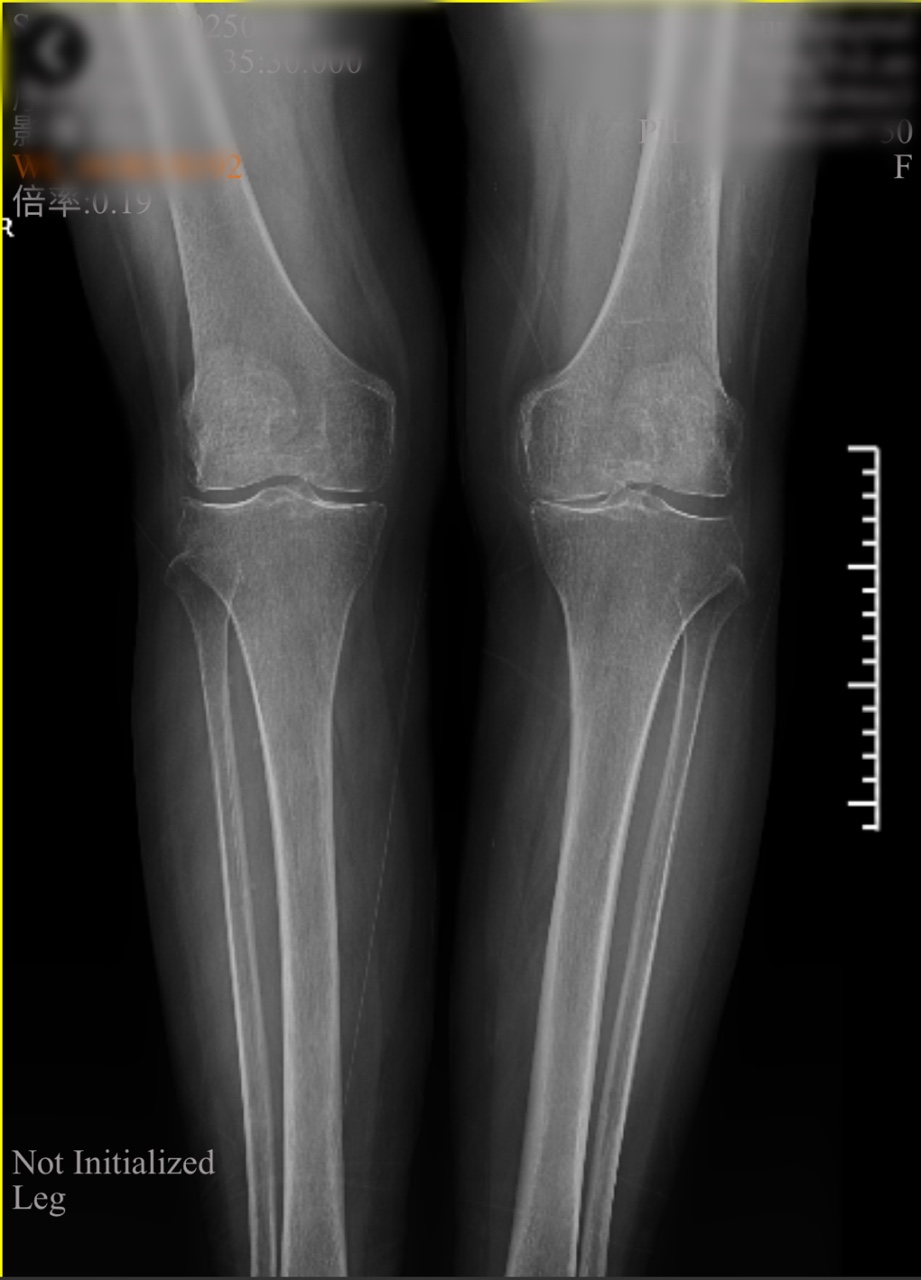

檢查室里,魏海清主任帶領(lǐng)團(tuán)隊(duì)為李阿姨做了詳細(xì)查體?!跋ドw內(nèi)翻畸形,軟骨剝脫,關(guān)節(jié)間隙明顯變窄......”影像學(xué)檢查證實(shí)了醫(yī)生的判斷:左膝關(guān)節(jié)骨質(zhì)增生嚴(yán)重,關(guān)節(jié)面硬化,屈伸活動(dòng)已嚴(yán)重受限。